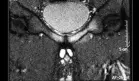

Ante la aparición de sangre fresca en el drenaje y el deterioro neurológico, se sospechó un hematoma extradural. Aunque la resonancia magnética no estuvo disponible por fallos técnicos, una tomografía computarizada con reconstrucción confirmó la presencia de un hematoma masivo (4,5 × 7 × 5 cm, aproximadamente 150 ml) en el sitio quirúrgico, con compresión significativa de la médula.

Se procedió a una reexploración quirúrgica urgente. Durante la intervención, se evidenció un hematoma brillante de origen arterial, con sangrado activo en dos puntos de los músculos paraespinales derechos, los cuales fueron controlados con coagulación. La médula se encontró indemne tras evacuar el hematoma y reabrir la duramadre, sin presencia de sangre en el espacio subdural.